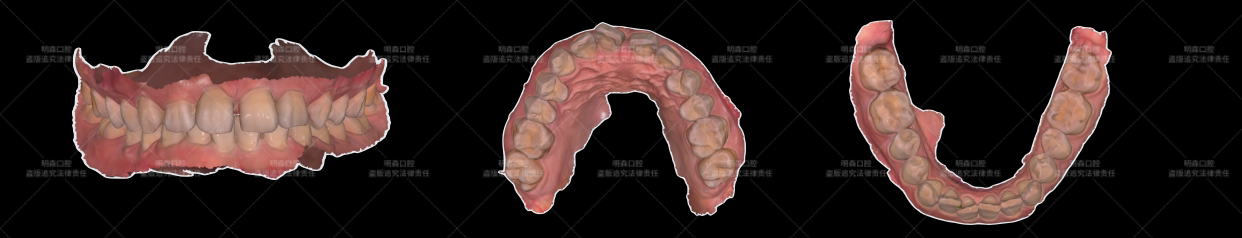

· 使用先进口腔数字扫描仪获取牙齿三维模型;

· 结合患者面型、笑容线、肤色、唇色及邻牙条件,进行数字化微笑设计(DSD),模拟修复后效果;

· 制作诊断蜡型规划贴面形态、大小及关闭缝隙的程度。